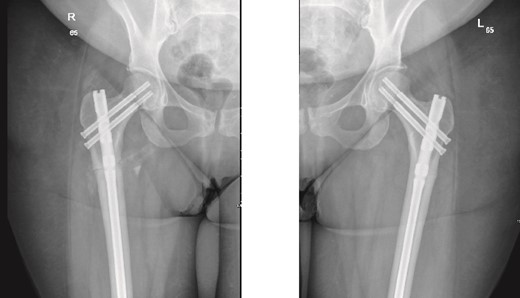

On examination, the patient was alert, oriented, and vitally stable. There were no open wounds on the right thigh, but mild tenderness was noted. The soft compartments were palpable, and the ankle range of motion was full. Distal neurovascular structures were intact. The left thigh showed no wounds or tenderness, and the hip range of motion was 0° to 60°, limited by pain in the right hip, as reported by the patient. Distal neurovascular structures were also intact on the left side. X-rays of both the right and left femurs, taken in the emergency department, are shown in Fig. 1.

Anteroposterior (AP) view of the right and left femurs pre-operative. With ismuths of 7.7 in R and 6.9 in L

Surprisingly, as seen in the X-rays in Fig. 1, the patient had a right subtrochanteric femur fracture and a stress line in the contralateral femoral cortex. While preparing and optimizing the patient for surgery, the endocrinology team was consulted regarding this presentation. According to their assessment, the patient’s laboratory findings were reassuring, and they confirmed that we could proceed with the surgical plan. Bone mineral density (BMD) testing was planned for afterward, and the endocrinology team would review the results. Surgery was scheduled for the following day.